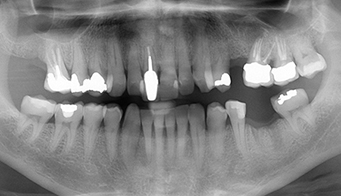

Your dental implant treatment begins with a consultation at Brener Clinic. Your implant diagnosis will include a consultation and thorough examination that includes a radiographic examination.

We take 3D Cone Beam CT Scans to assist with treatment planning. We also collect other records, such as facial photographs and videos, as well as digital impressions of your upper and lower jaws. A thorough medical history is taken so we can communicate with your doctor and specialist medical team if necessary.

This allows us to digitally design your smile and plan the surgery.

i) Missing tooth

ii) Implant placed

iii) New tooth replacement placed